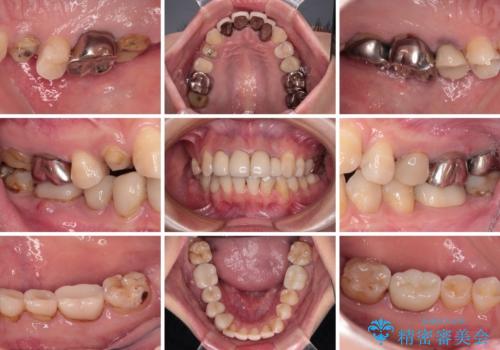

以前の治療箇所が痛む 全顎的なむし歯治療

- 結婚式に向けて、前歯のセラミックを作り替えたいとのことで来院された患者様です。

むし歯で神経を取り除いたことをきっかけに、前歯をセラミックにしたそうですが、金属の縁が見えてきたり、内側に引っ込んでいた歯を強引に前に出しことで汚れが溜まったりと、不具合を感じているとのことでした。

また、奥歯にも痛みがあったり治療途中で放置されていたりと、全顎的な治療が必要な状況でした。

結婚式が近いことから、前歯は舌側に転位している歯は抜歯してブリッジにすることで外見と清掃性を改善し、速やかにオールセラミッククラウンにて補綴治療を行うこととしました。

その後、奥歯は痛みのある部分から少しずつ、根管治療やインプラント治療などを行うこととしました。